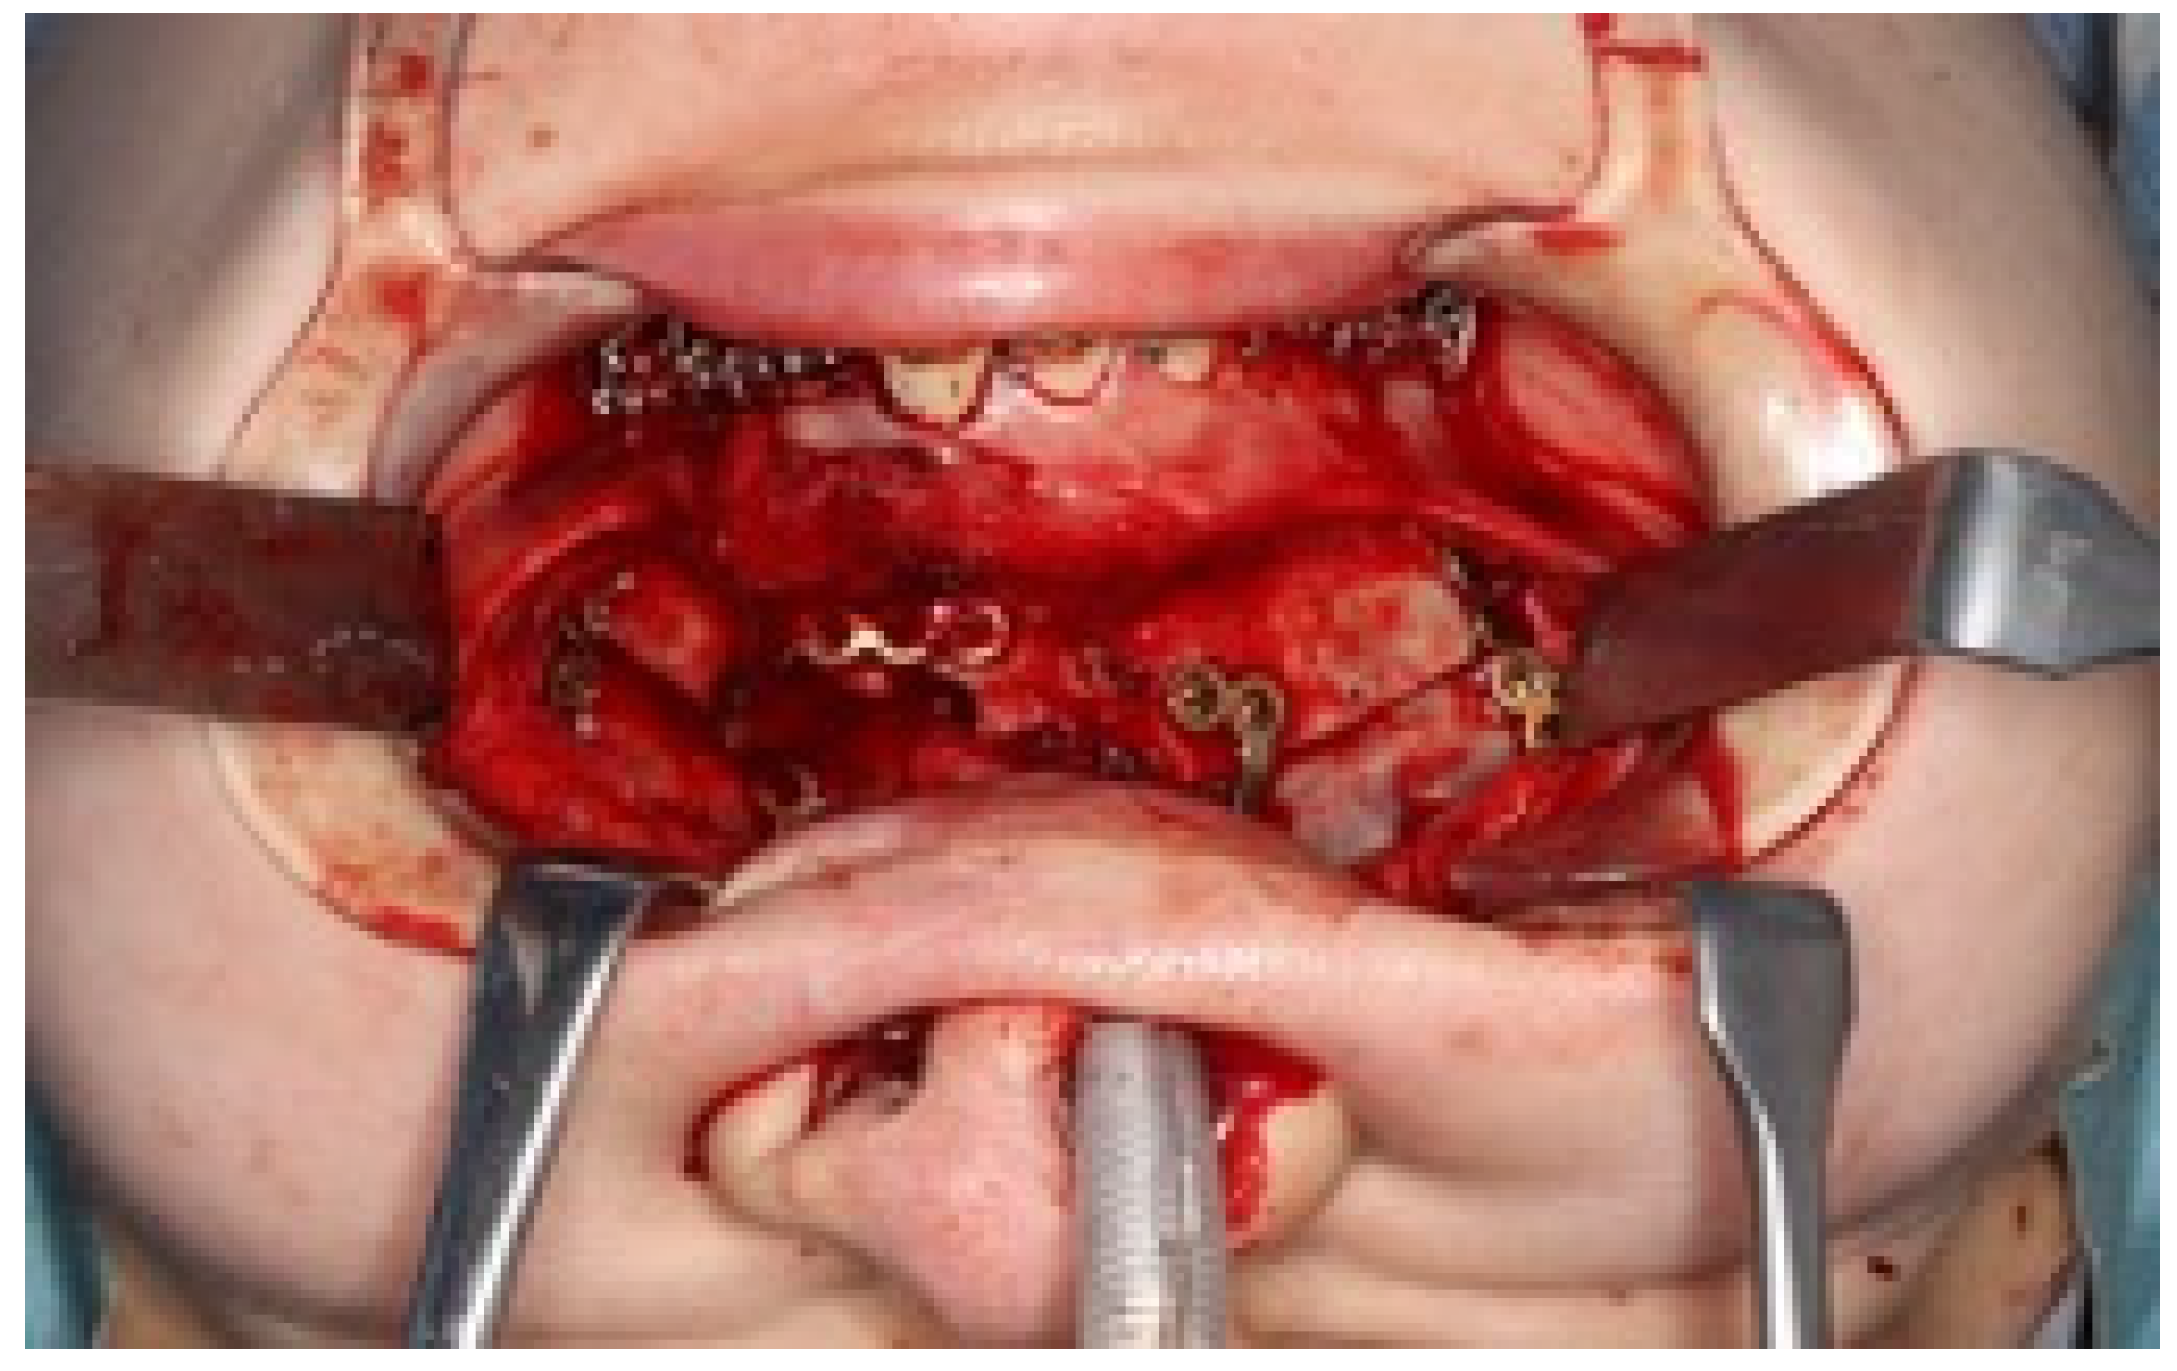

In the mandible, SSRO was performed, involving an 8.0° right rolling movement and a 2.0 mm parallel movement to the left to correct the deviation. In addition, to address the protrusion of the lower lip, a setback of 4.0 mm was performed to enhance the facial profile. Postoperatively, surgical splinting and intermaxillary fixation were performed. For bone fixation of the maxilla and mandible, titanium plates were used, with horizontal plate fixation implemented in the maxilla to improve the bone width (Figure 8). Notably, for 5 months postoperatively, intermaxillary elastics were used to stabilize the occlusion, and the multi-bracket system was removed 14 months post-surgery. During this period, at the patient’s request, a splint retainer was fabricated, and the brackets were removed to commence the retention phase.

Figure 8.

Under surgical orthodontic treatment.